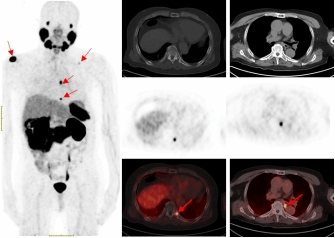

一名75的岁男性患者自2019年确诊前列腺癌后,先后接受过两次内分泌治疗及前列腺癌根治术的综合治疗。在术后两年的复查中发现血PSA持续升高,CT检查和全身骨显像检查均未发现明显异常,医生建议随诊,患者来到江南大学附属医院要求进一步检查。经核星空(中国)科68Ga-PSMA PET/CT检查后结果显示,双侧肩胛骨、左侧第9后肋、第2腰椎及纵隔淋巴结均已存在癌症转移。